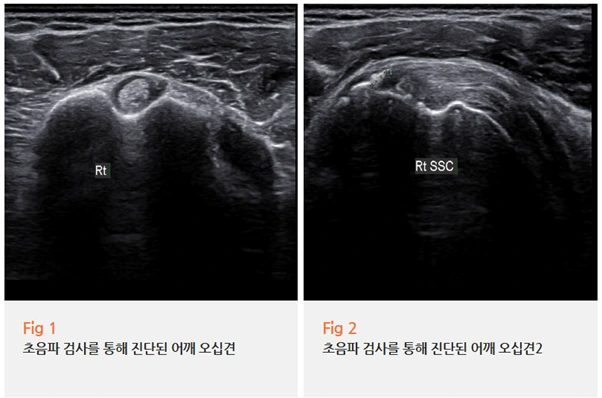

저희 콕통증의학과에서는 정확한 진단을 위해 우선 당일 초음파 검사를 진행했어요.

초음파 검사는 실시간으로 어깨 내 구조물의 상태를 확인할 수 있는 검사예요.

회전근개의 파열 여부, 관절낭의 두께와 상태, 활액막의 염증 유무까지

숙련된 의료진이 초음파로 확인하면 오십견 여부를 상당히 정밀하게 파악할 수 있습니다.

저희는 영상의학과 전문의가 직접 초음파 검진을 먼저 시행하고,

이후 통증의학과 전문의가 다시 한번 초음파를 확인하며 치료를 진행하는 방식으로 운영하고 있어요.

초음파 결과를 확인해 보니, 이 환자분은 어깨 오십견으로 진단이 되었고

주사치료를 중심으로 한 비수술적 치료로도 충분히 호전 가능성이 높은 상태였어요.

그래서 MRI 촬영 없이 치료를 진행하기로 했습니다.